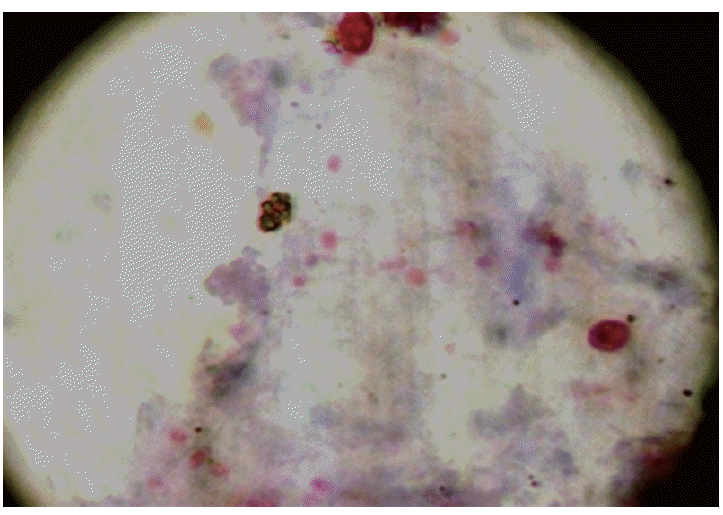

The median age for the cases (n=200) and controls (n=200) was 36 years (range 19-59) and 39 years (19-65), respectively (Table 1). Morphologically, a total of 123 out of 400 patients were positive for any kinds of intestinal parasites. The cumulative number of positive patients was 145 because of multiple infections. The parasite species included Cryptosporidium spp. (n=13), C. cayetanensisi (n=3), C. belli (n=15), Strongyloides stercoralis (n=5), G. lamblia (n=32), E. histolytica/E. dispar (n=15), Ascaris lumbricoides (n=2), Hymenolepis nana (n=10), Entamoeba coli (n=11), Endolimax nana (n=9), and B. hominis (n=30). The environmentally resistant oocysts of Cryptosporidium spp. and C. cayetanensisi measured 4-6 µm and 8- 10 µm, respectively (Fig. 1A, B), whereas, oocysts of C. belli were oval and measured 20-30×10-15 µm in size (Fig. 1C). Spores of microsporidia appeared as small pink dots measuring 1-2 µm in size (Fig. 2). All the measurements were done using the standard micrometry technique.